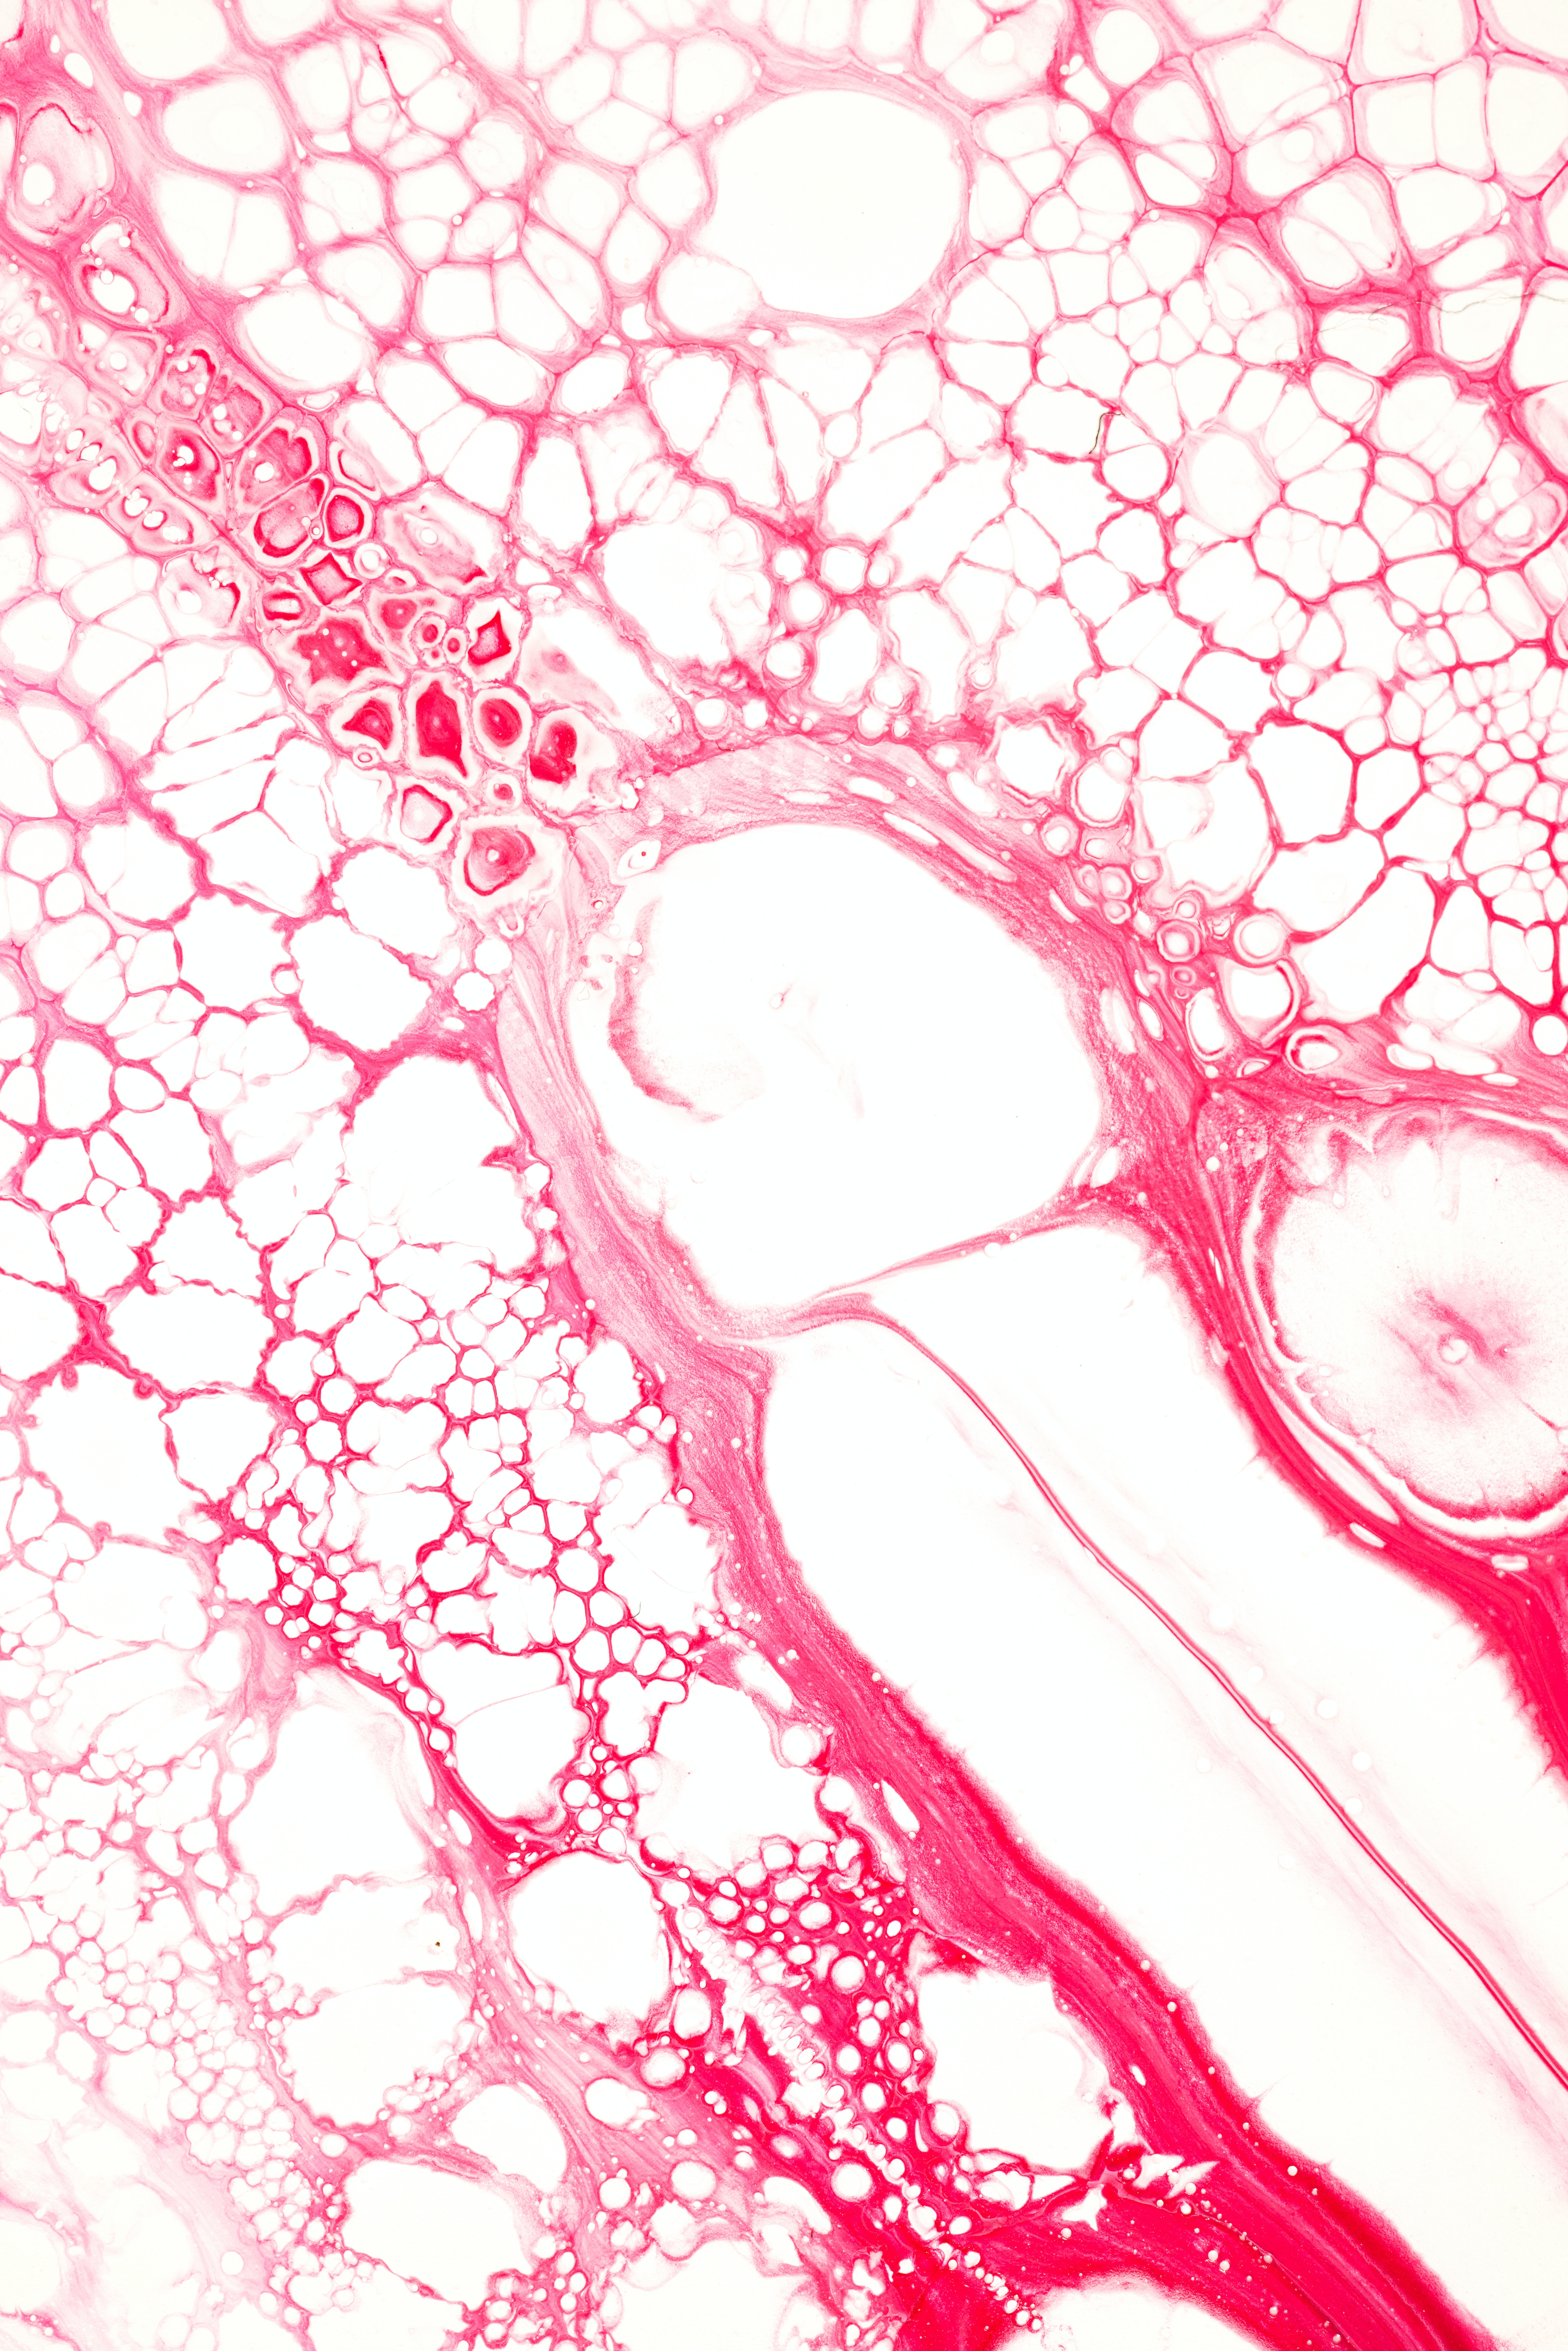

정상인의 혈액을 혈맥분석기로 보면,

혈액이 동글동글하고 점점이 ‘기’가 많이 박혀 있어 활발하게 움직입니다.

그런데 중풍 환자의 피를 보면 혈구 모양이 동그랗지 않고 어혈과 불순물이 많습니다.

섬유질 같은 지방 덩어리, 콜레스테롤 덩어리 등 찌꺼기가 많아

혈액이 끈적끈적하고, ‘기’도 활발하지 않습니다.

즉, 정상인은 온몸의 기와 혈이 잘 순환되지만,

중풍 환자는 기와 혈이 뭉쳐서 순환이 잘 이루어지지 않습니다.